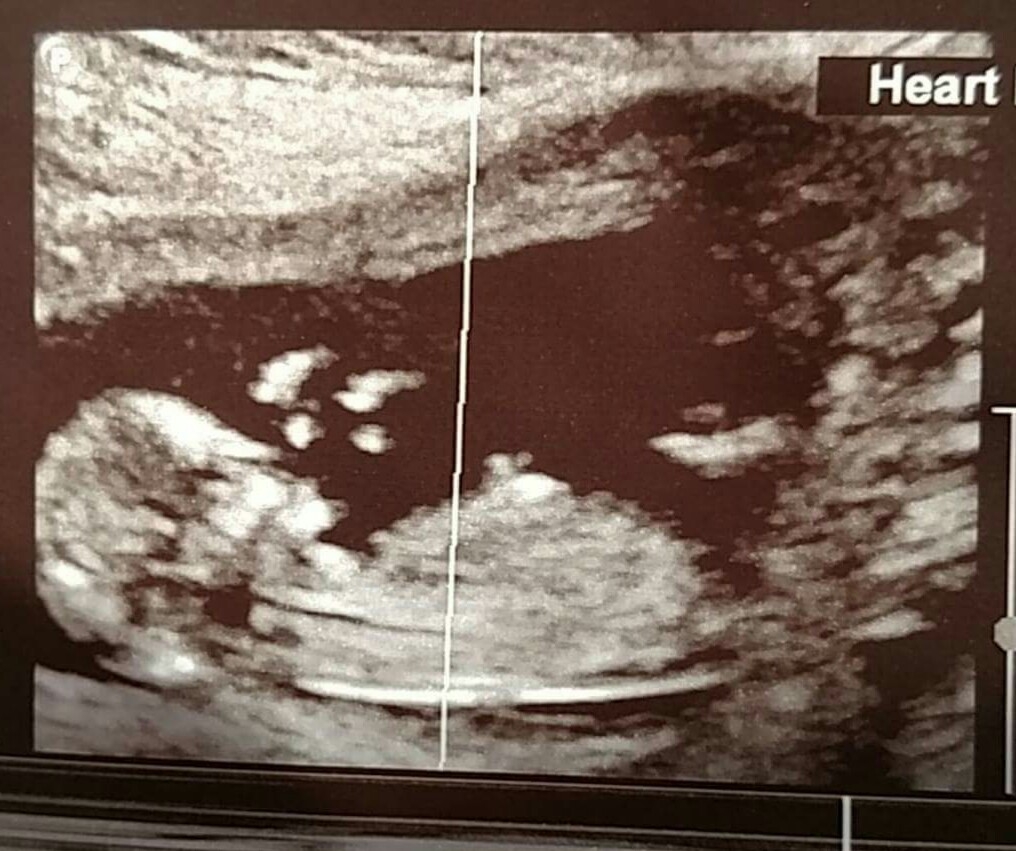

I had my MFM appointment today for my NT scan and have another US tomorrow with my regular OB. Baby was very stubborn but cooperated in the end so we could get everything we needed. My consult also went very well which was wonderful

Bonus: Looks like this baby is a boy!! Our third and we couldn't be more thrilled. DH and I love our boys more than anything and can't wait to add another.

The technician said they are worried if the fluid measures more then 3 and we were at 1.7

The baby was dancing around just like his/her mama complete Elaine style!! He/she even shifted their head from the left side of my belly to the right. This is one active baby!!